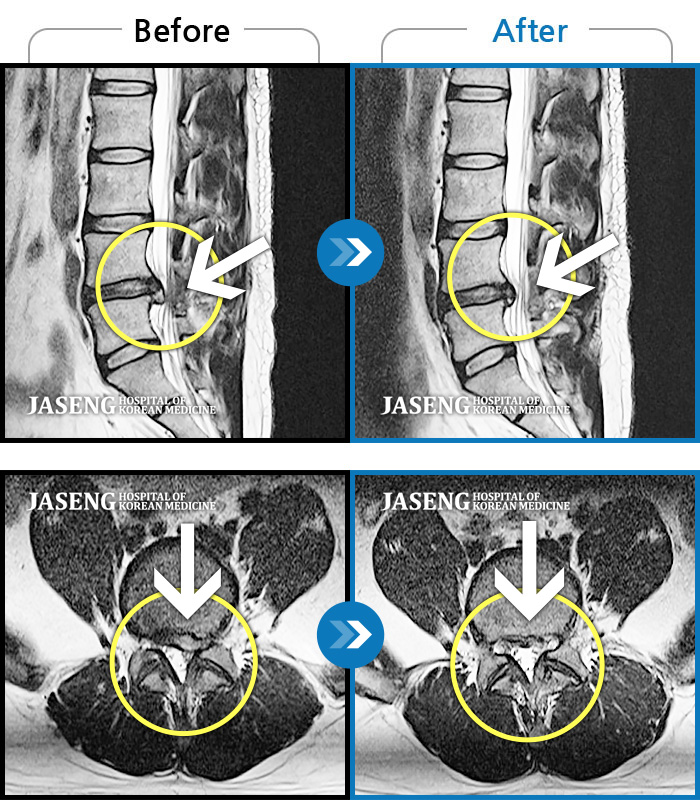

MRI 치료사례

어떠한 자세를 취해도 통증이 있고 왼쪽 엉덩이, 다리 통증으로 잠을 자주 깬다.